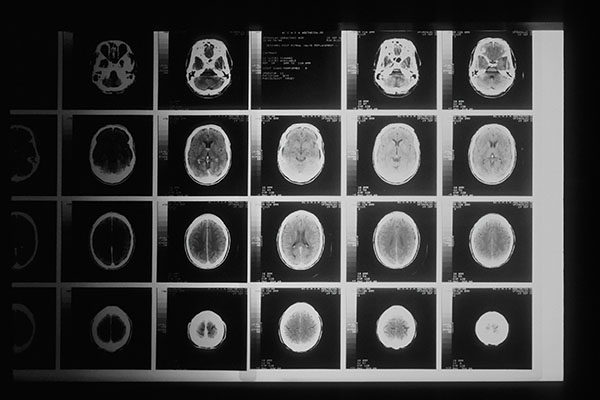

哮喘并不是什么好事,它是一种会导致气道狭窄和炎症的呼吸系统疾病。但是,有哮喘的人群患脑部肿瘤的概率似乎比其他人更低。如今,圣路易斯华盛顿大学医学院的研究人员认为他们已经发现了原因。

这与名为T细胞的免疫细胞的行为有关。当人类或是小鼠患有哮喘时,体内的T细胞便会被激活。在对小鼠的新研究中,研究人员发现,哮喘引起的T细胞应答会导致肺部炎症,但却也阻止了大脑肿瘤的生长。呼吸道的坏事可能是大脑的福音。

在线发表于《自然·通讯》(Nature Communications)杂志上的研究指出,重新编码大脑肿瘤患者的T细胞使其表现地更像哮喘患者的T细胞有望成为大脑肿瘤的新疗法。